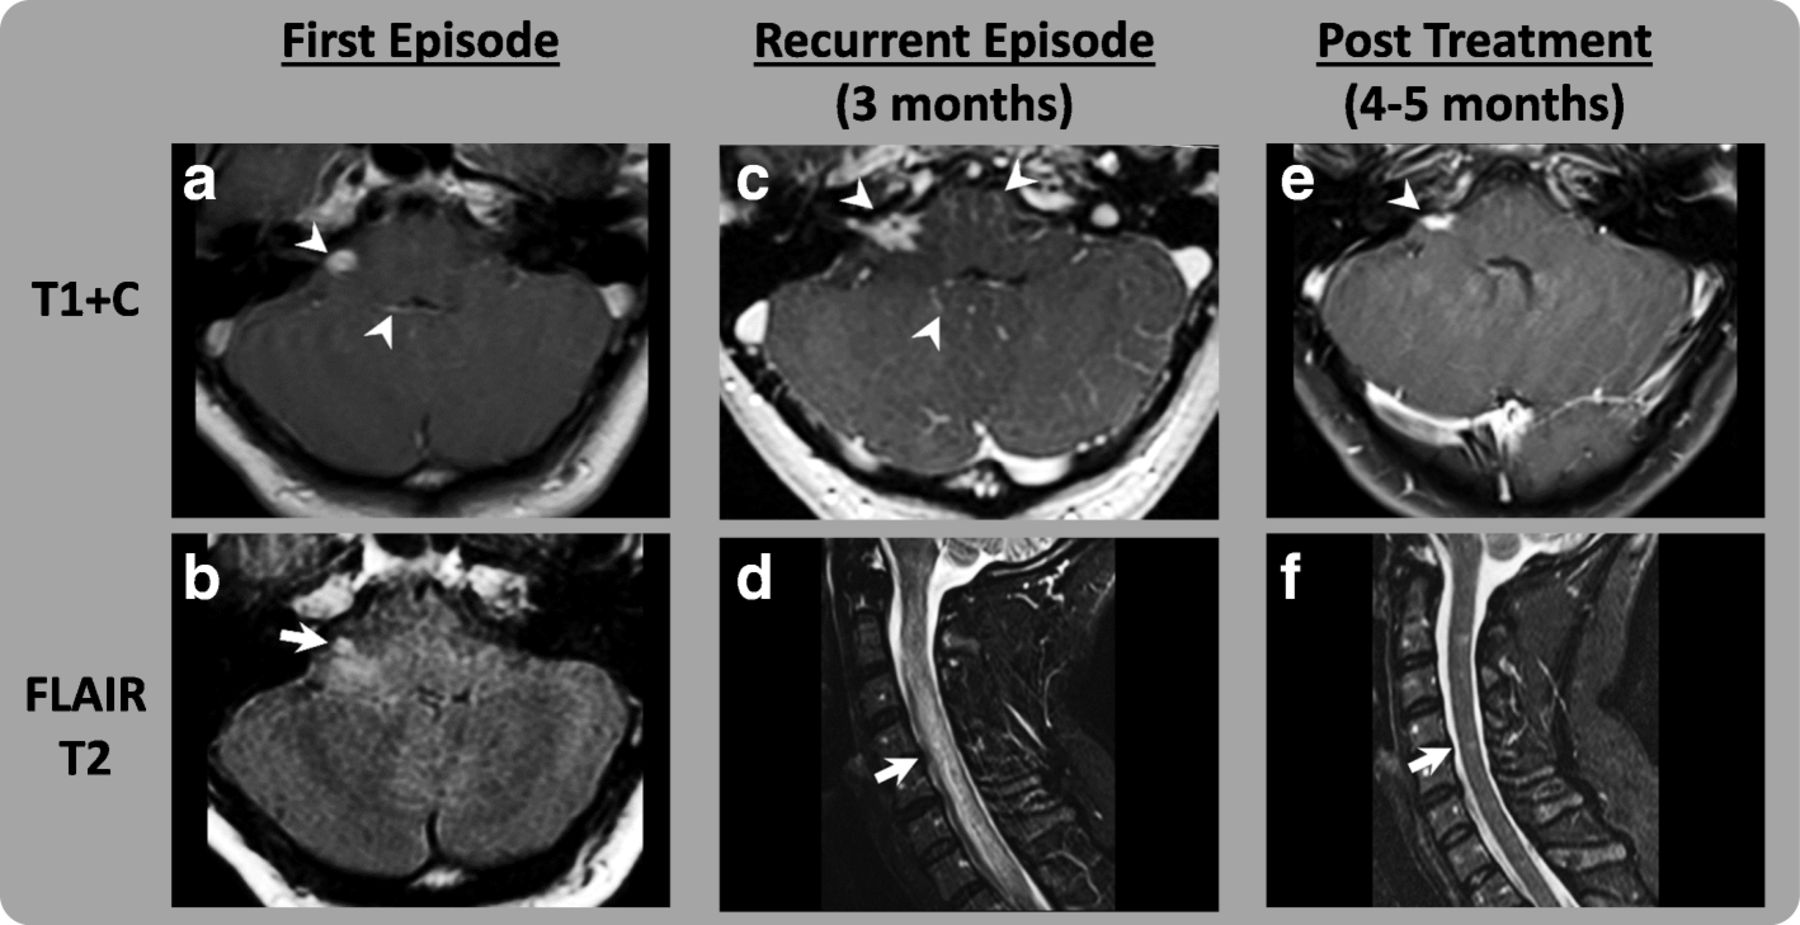

Neurologic Immune Related Adverse Events Associated With Adjuvant

Neurologic Immune Related Adverse Events Associated With Adjuvant